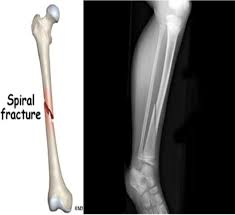

4) spiral fracture:=

Spiral fracture ને torsion fracture કહેવામાં આવે છે.

આ બોનફેક્ચર કહેવામાં આવે છે.

આ મુખ્યત્વે ટ્વીસ્ટીંગ ફોર્સ લાગવાના કારણે જોવા મળે છે.